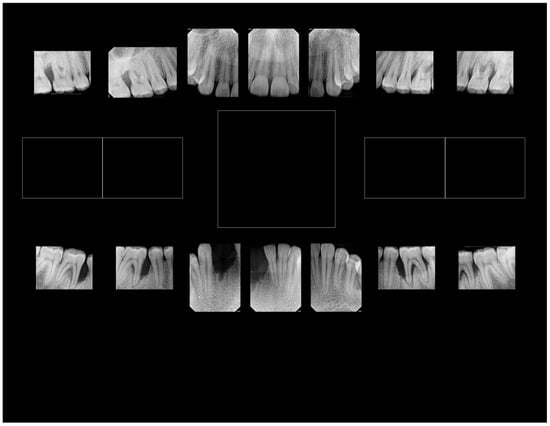

6. Distinct Characteristics of LAgP and an Alternative Approach for Assessing Treatment Success

- (A)

- Distinct Characteristics of LAgP: An Illustrative Case.